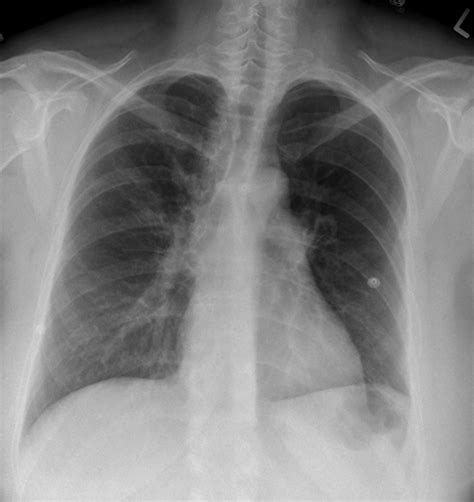

Chest X-Ray

A Lung Embolism X Ray is often the first imaging test performed. It can help rule out other conditions that may cause similar symptoms, such as pneumonia or a collapsed lung. However, as mentioned earlier, a chest X-ray alone is not sufficient to confirm a lung embolism.